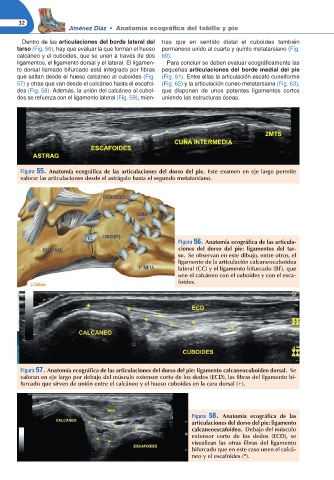

Figura 56. Anatomía ecográ ca de las articula-

CALCÁNEO ciones del dorso del pie: ligamentos del tar-

so. Se observan en este dibujo, entre otros, el

ligamento de la articulación calcaneocuboidea

5° META lateral (CC) y el ligamento bifurcado (BF), que

une el calcáneo con el cuboides y con el esca-

foides.